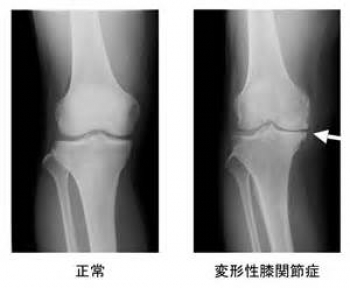

第一回の膝の病気は、本当に多い”変形性膝関節症”についてお話させてもらいます。

筋力低下、加齢、肥満などにより、膝軟骨がすり減り、半月板のかみ合わせが緩むことにより、膝の変形を起こす病気です。

もともと、膝の軟骨や半月板は、クッションの役目をしますが、その膝軟骨や半月板が長期間に少しずつすり減り変形することで起こります。

問診、視診、触診、関節液検査、X線検査、血液検査などにより判断します。